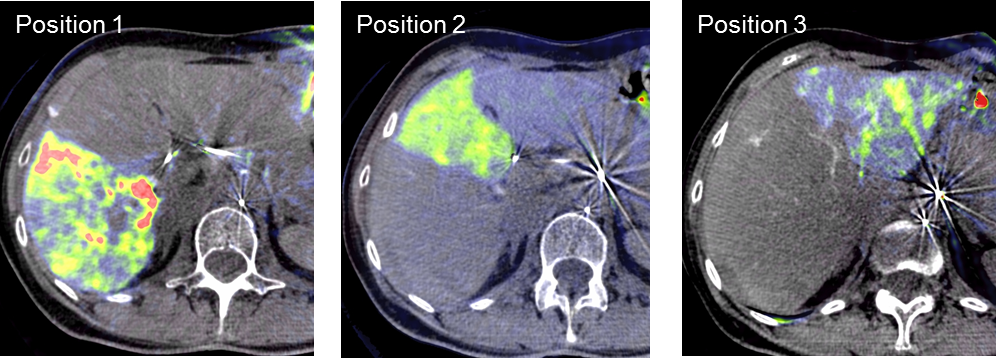

Die Selektive Interne Radiotherapie (SIRT) wird in der Fachliteratur auch Radioembolisation (RE) genannt. Hierbei werden gezielt kleine, radioaktive Kügelchen, sog. Mikrosphären, über den Katheter (siehe TACE) von mehreren Positionen in der Leber mit dem Blutstrom in das gut durchblutete Tumorgewebe gebracht und bleiben dort in den kleinen Gefäßen "stecken", die den Tumor ernähren. Von dort bestrahlt das in den Kügelchen enthaltene radioaktive Element Yttrium-90 über mehrere Tage hinweg das Tumorgewebe und zerstört es selektiv. Dieses Verfahren kann bei Leberkrebs oder -metastasen eingesetzt werden, wenn die Herde trotz Chemotherapie weiter wachsen und nicht chirurgisch oder mittels RFA und TACE behandelbar sind.

Das Verfahren wird von der interventionellen Radiologie zusammen mit der Partnerabteilung der Nuklearmedizin sowie den entsprechenden Partnerkliniken geplant und durchgeführt.

Abbildung Körper: Schematische Darstellung des Zugangsweges bei SIRT-Therapie über die Leistenarterie. Die arteriellen tumorversorgenden Gefäße in der Leber werden selektiv dargestellt und von dort wird die Therapie lokal appliziert. (Bildrechte beim Thieme-Verlag!)